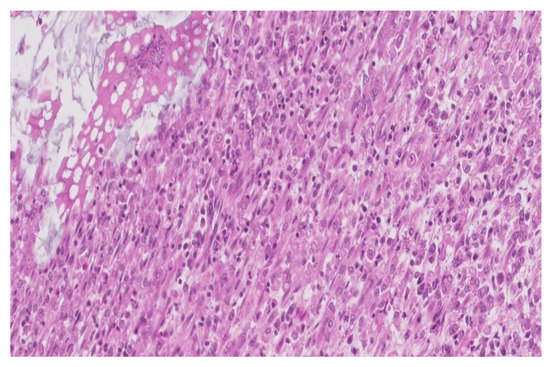

Furthermore, the anatomopathological department recommended immunohistochemical tests for a precise and definitive diagnosis of our patient.

The result of the immunohistochemical tests confirmed that the inflammatory infiltrate was predominantly comprised of:

- macrophages (positive CD68)-illustrated in the Figure 4

Figure 4. Positive CD68 in the macrophage infiltrate (×200). - with rare dispersed T lymphocytes (positive CD3),

- rare B lymphocytes (alpha positive CD20, CD79) especially in the lamina propria,

- rare plasmacytes (alpha positive CD79),

- as well as rare mast cells (positive tryptase).

Additionally, most macrophages were positive for CD204 (MSR1), a receptor that plays a role in phagocytosis (Figure 5).

Alpha-SMA was positive in the smooth muscle cells, from the level of the muscularis mucosae and the own muscle, being negative in the inflammatory cells.

The most distinctive histological feature for the diagnostic of malakoplakia is represented by the Michaelis-Gutmann bodies, which are concentric, basophilic, round or oval lamellae, with a diameter of 5 to 10 µm, included in the cytoplasm of the histocytes, known as von Hansemann cells. These inclusions are generally positive PAS and von Kossa, being composed of a glycolipid matrix, probably of a specific microorganism and are covered with a calcium and iron layer. The foamy histiocytes are mainly dispersed in the lamina propria of the mucosa, next to rare lymphocytes and occasionally to multinucleated giant cells. Therefore, the precise diagnosis of this pathology can only be stated after microscopic examination, in the usual hematoxylin eosin staining, as well as by using the mentioned special staining, or by performing immunohistochemical tests [11].